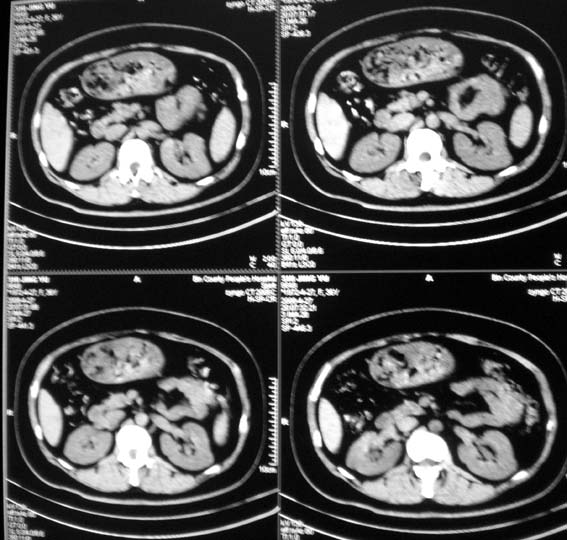

标题: CT13126:腰痛,肾区痛。 [打印本页]

标题: CT13126:腰痛,肾区痛。

女,36岁,腰痛,肾区痛曾有肾囊肿史。

髓质海绵肾?建议mr。

上腹部平扫未见明显异常。

中上腹部ct平扫未见明显异常。